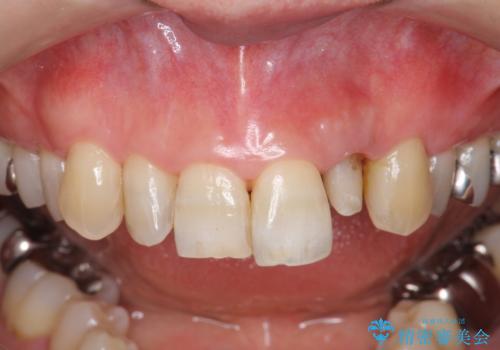

- 目立つ前歯の著しい変色の改善を求めて来院されました。

根管治療が為されたまま、クラウンの装着が行われず変色し審美障害を来している状態です。

維持を保つためのファイバーコア築盛を行い、精密なジルコニアクラウン製作を行います。